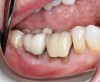

Fig 11. Buccal view of mandibular right second molar.

Figure 11

A 68-year-old male patient presented with a failing lower right second molar and retained third molar and was seeking implant restoration at the second molar site (Figure 11 and Figure 12). The patient's medical history was significant for hypertension and cardiac arrhythmia under good control.